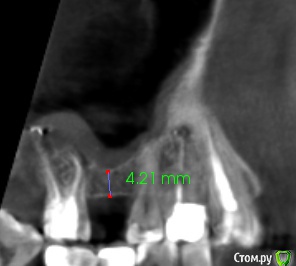

Fin Опубликовано 20 марта, 2020 Поделиться Опубликовано 20 марта, 2020 Здравствуйте коллеги.Планируется имплантация в области 1.6. Но зуб 1.7 с небольшой кистой в гайморовой пазухе, перелечить невозможно СО пазухи в этой области отечна.. Пациенту требуется синус лифтинг. Думаю что нужно удалять 1.7 и после делать имплантацию с ЗСЛ или ОСЛ. На данный момент пациент немного противится, поэтому и решил спросить. Как бы вы поступили, поставили бы короткий имплантат, или ЗСЛ без удаления 7ки. Буду благодарен Вашим ответам. Ссылка на комментарий

Fin Опубликовано 20 марта, 2020 Автор Поделиться Опубликовано 20 марта, 2020 Удалил бы, конечно Тут транскрестально поднять не проблема, не надо короткий, можно даже 10, пожалуй, но зуб этот надо удалять по любым показаниям. Пациент если этого не понимает, то я бы просто отказалПациент вполне адекватный, просто к нам попал после ужасного эндодонтического лечения в другой клинике. Только 2 зуба удалось перелечить, 4 зуба удалили из-за осложнений эндодонтического лечения и уже поставили 3 импланта. А тут еще 4 ка и 7ка на выход просятся. Вот он и просит всеми способами попытаться сохранить до последнего 7ку, а я вас спрашиваю т.к. не вижу другого выхода))Вы бы удалили, через 4 месяца ЗСЛ и пару 5 на 10 поставили? Короткий я не особо хочу, только как вариант. Ссылка на комментарий

Fin Опубликовано 20 марта, 2020 Автор Поделиться Опубликовано 20 марта, 2020 Я бы посмотрел кт в области зуба) может и одномоментно Если отсроченно, то 2 месяца. Но если терапевт не готов на эндодонтию - то удалил бы в любом случае А если терапевт берётся лечить - то я бы подождал две недели после пломбировки и посмотрел симптоматику, дальше закрытым. Если брать винт пошире, то апертура будет почти как латеральная, дно ровное, если пробку костную продавите - поднять несложно. Лечить пытались, не получилось. Не очень понял, вы имеете ввиду поднять имплантом?Я стараюсь вогнутым остеотомом подстукивая продавливать и им же по возможности поднимать, но обычно это до 3-4 мм, больше побаивался.Благодарю за совет. Ссылка на комментарий